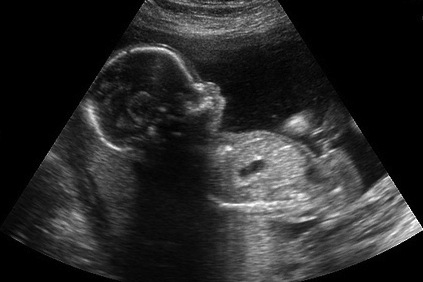

Hugo: To be fair, men have a fertility window too, though it’s less well-known and less obvious. The research connecting older fathers to everything from autism to an increased risk of miscarriage is pretty well-established. We can still father healthy biological children into our dotage, but we’re kidding ourselves if we imagine that our sperm hasn’t been degraded with the rest of us.

This is one reason why younger women should be just a bit wary of having kids with much older men. Not only is there an increased risk of birth defects, the brutal truth is that we’re not going to be around as long.

Interestingly, mothers of newborns today are older than ever before. That may not have much impact on men’s lives, but it’s had a pretty profound impact for women in terms of complications and challenges with fertility (and increased use of things like IVF).

And teaching men about the real impact of “aging sperm” is not a small issue. All the research points to a real decline in quality of swimmers after 40 (if not earlier); men do well to realize that they have a biological clock too. We’re more like women in this regard than we realize. Education is the answer here.